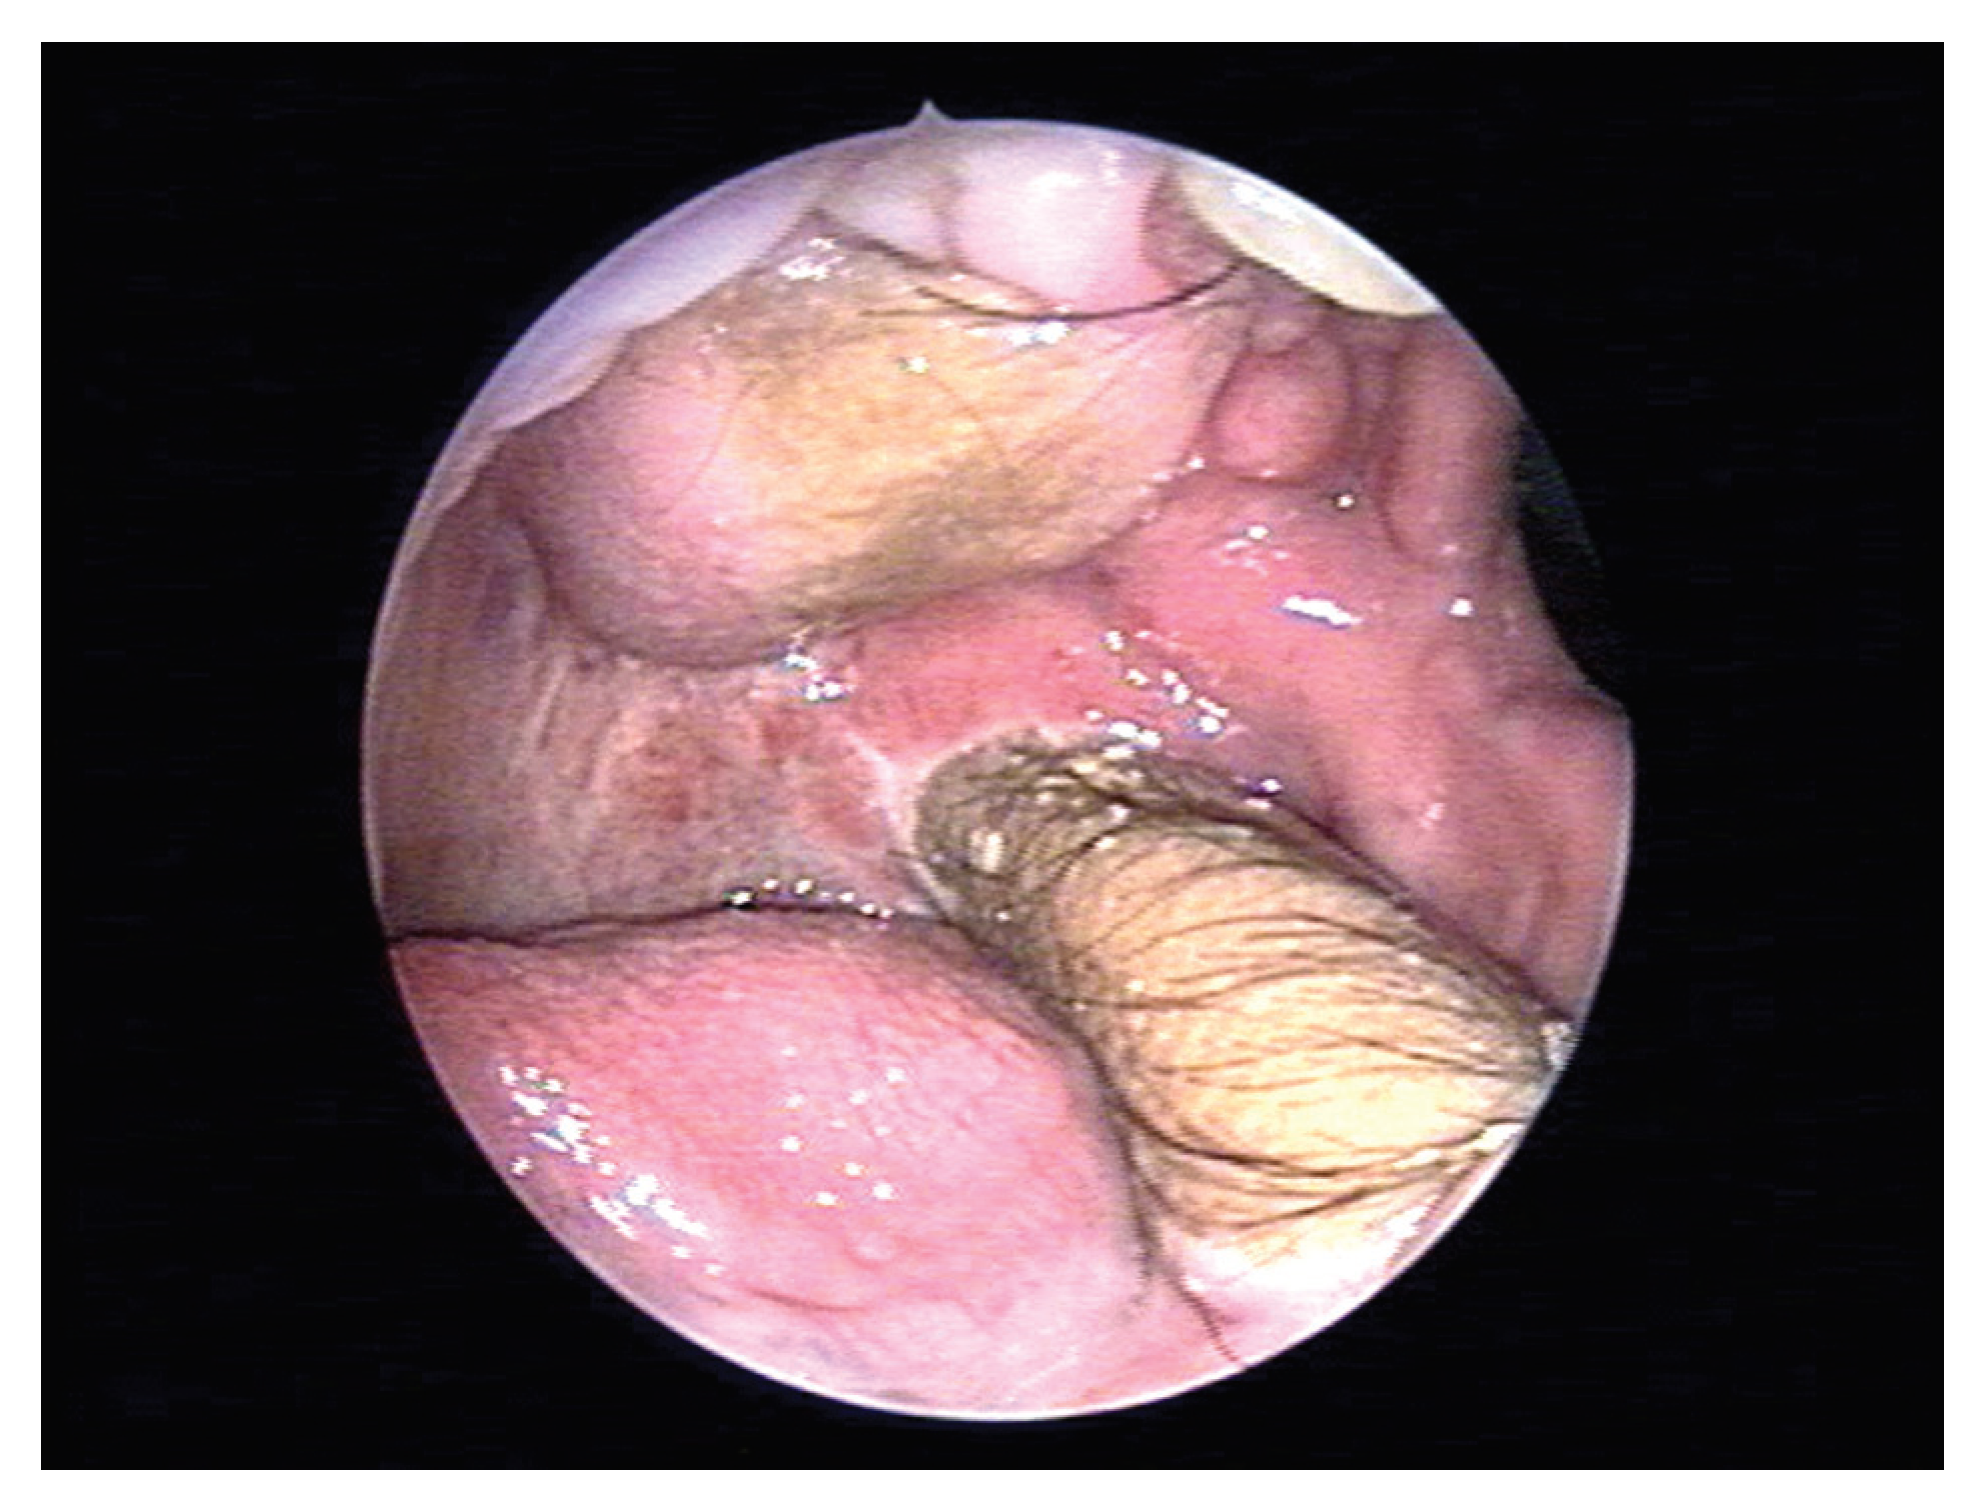

Figure 6. Endoscopic view of oral cavity showing the status 6 months postoperatively.